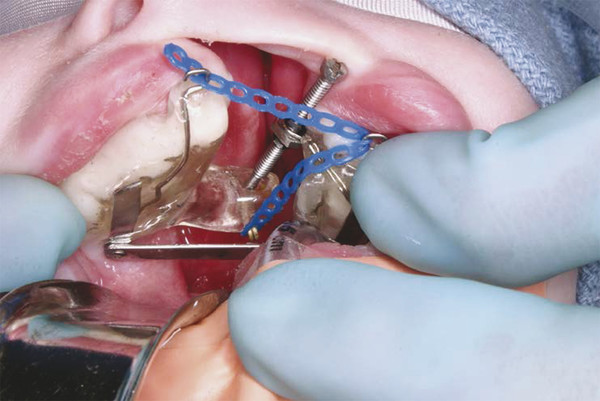

On the day of operation, the infant must have nothing by mouth for 6 hours in advance. An oral endotracheal tube is inserted; the patient is prepped and draped for a sterile procedure, and the oropharynx is packed. The appliance is tried in the mouth to ensure that it fits well; the pins are inserted in slots through the acrylic using a needle holder and set in place by using an orthodontic band seater and a surgical mallet (Fig. 12‑5 and Fig. 12‑6).

Each pin is approximately 15 mm in length, with a spring loop bend at the head, which will be compressed into the slot in the acrylic to ensure that the pin cannot be lost. When the pins are fully seated and the appliance is in position, the pin slots are covered with a small amount of restorative composite to ensure that the pin will not come out of the appliance, and the composite is set with a curing light. The appliance is activated by rotation of a screw within the cleft site, which extends on a diagonal from the anterior of the lesser segment posteriorly to a receiving cup at the posterior aspect of the greater segment. Initial activation requires 4 to 5 full (360-degree) turns, until the screw is firmly engaged in the cup. The elastic chain extending from the posterior aspect of the greater segment to the anterior aspect of the lesser segment and across to a hook on the greater segment is activated (Fig. 12‑7).